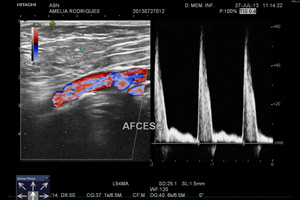

Seguindo o principio da ecografia, e utilizando a técnica de Doppler este exame permite determinar patologias arteriais e/ ou venosas ( ex: estreitamento e entupimento das artérias e coágulos das veias).

Mostra-nos imagens e sons das artérias e /ou veias.

Podem ser realizados (entre outros) estudos por eco-Doppler: Carotídeo; Membros superiores e inferiores.